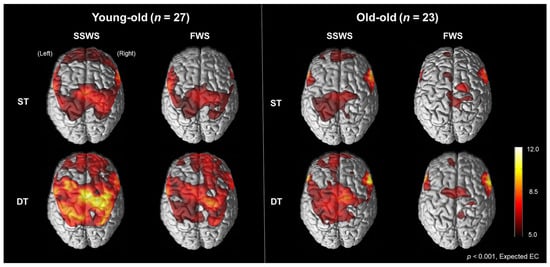

Figure 2 illustrates cortical activation patterns during walking in each condition in the young-old and the old-old. In the SPM analysis results, cortical activation measured by oxyHb concentration was increased during the DT conditions compared with the ST conditions but decreased during the FWS conditions compared with the SSWS conditions on the bilateral M1-leg, SMC, PM, SMA, and dlPFC in both the young-old and the old-old. Cortical activation was lower in the old-old than the young-old.

Figure 2.

Cortical activation patterns during walking in the young-old and the old-old. Cortical activities measured by oxyHb concentration were increased during dual-task walking compared with single-task walking but decreased during fast-walking speed compared with self-selected walking speed in the bilateral M1-leg, SMA, and dlPFC in both the young-old and the old-old elderly. ST, single-task; DT, dual-task; SSWS, self-selected walking speed; FWS, fast walking speed.